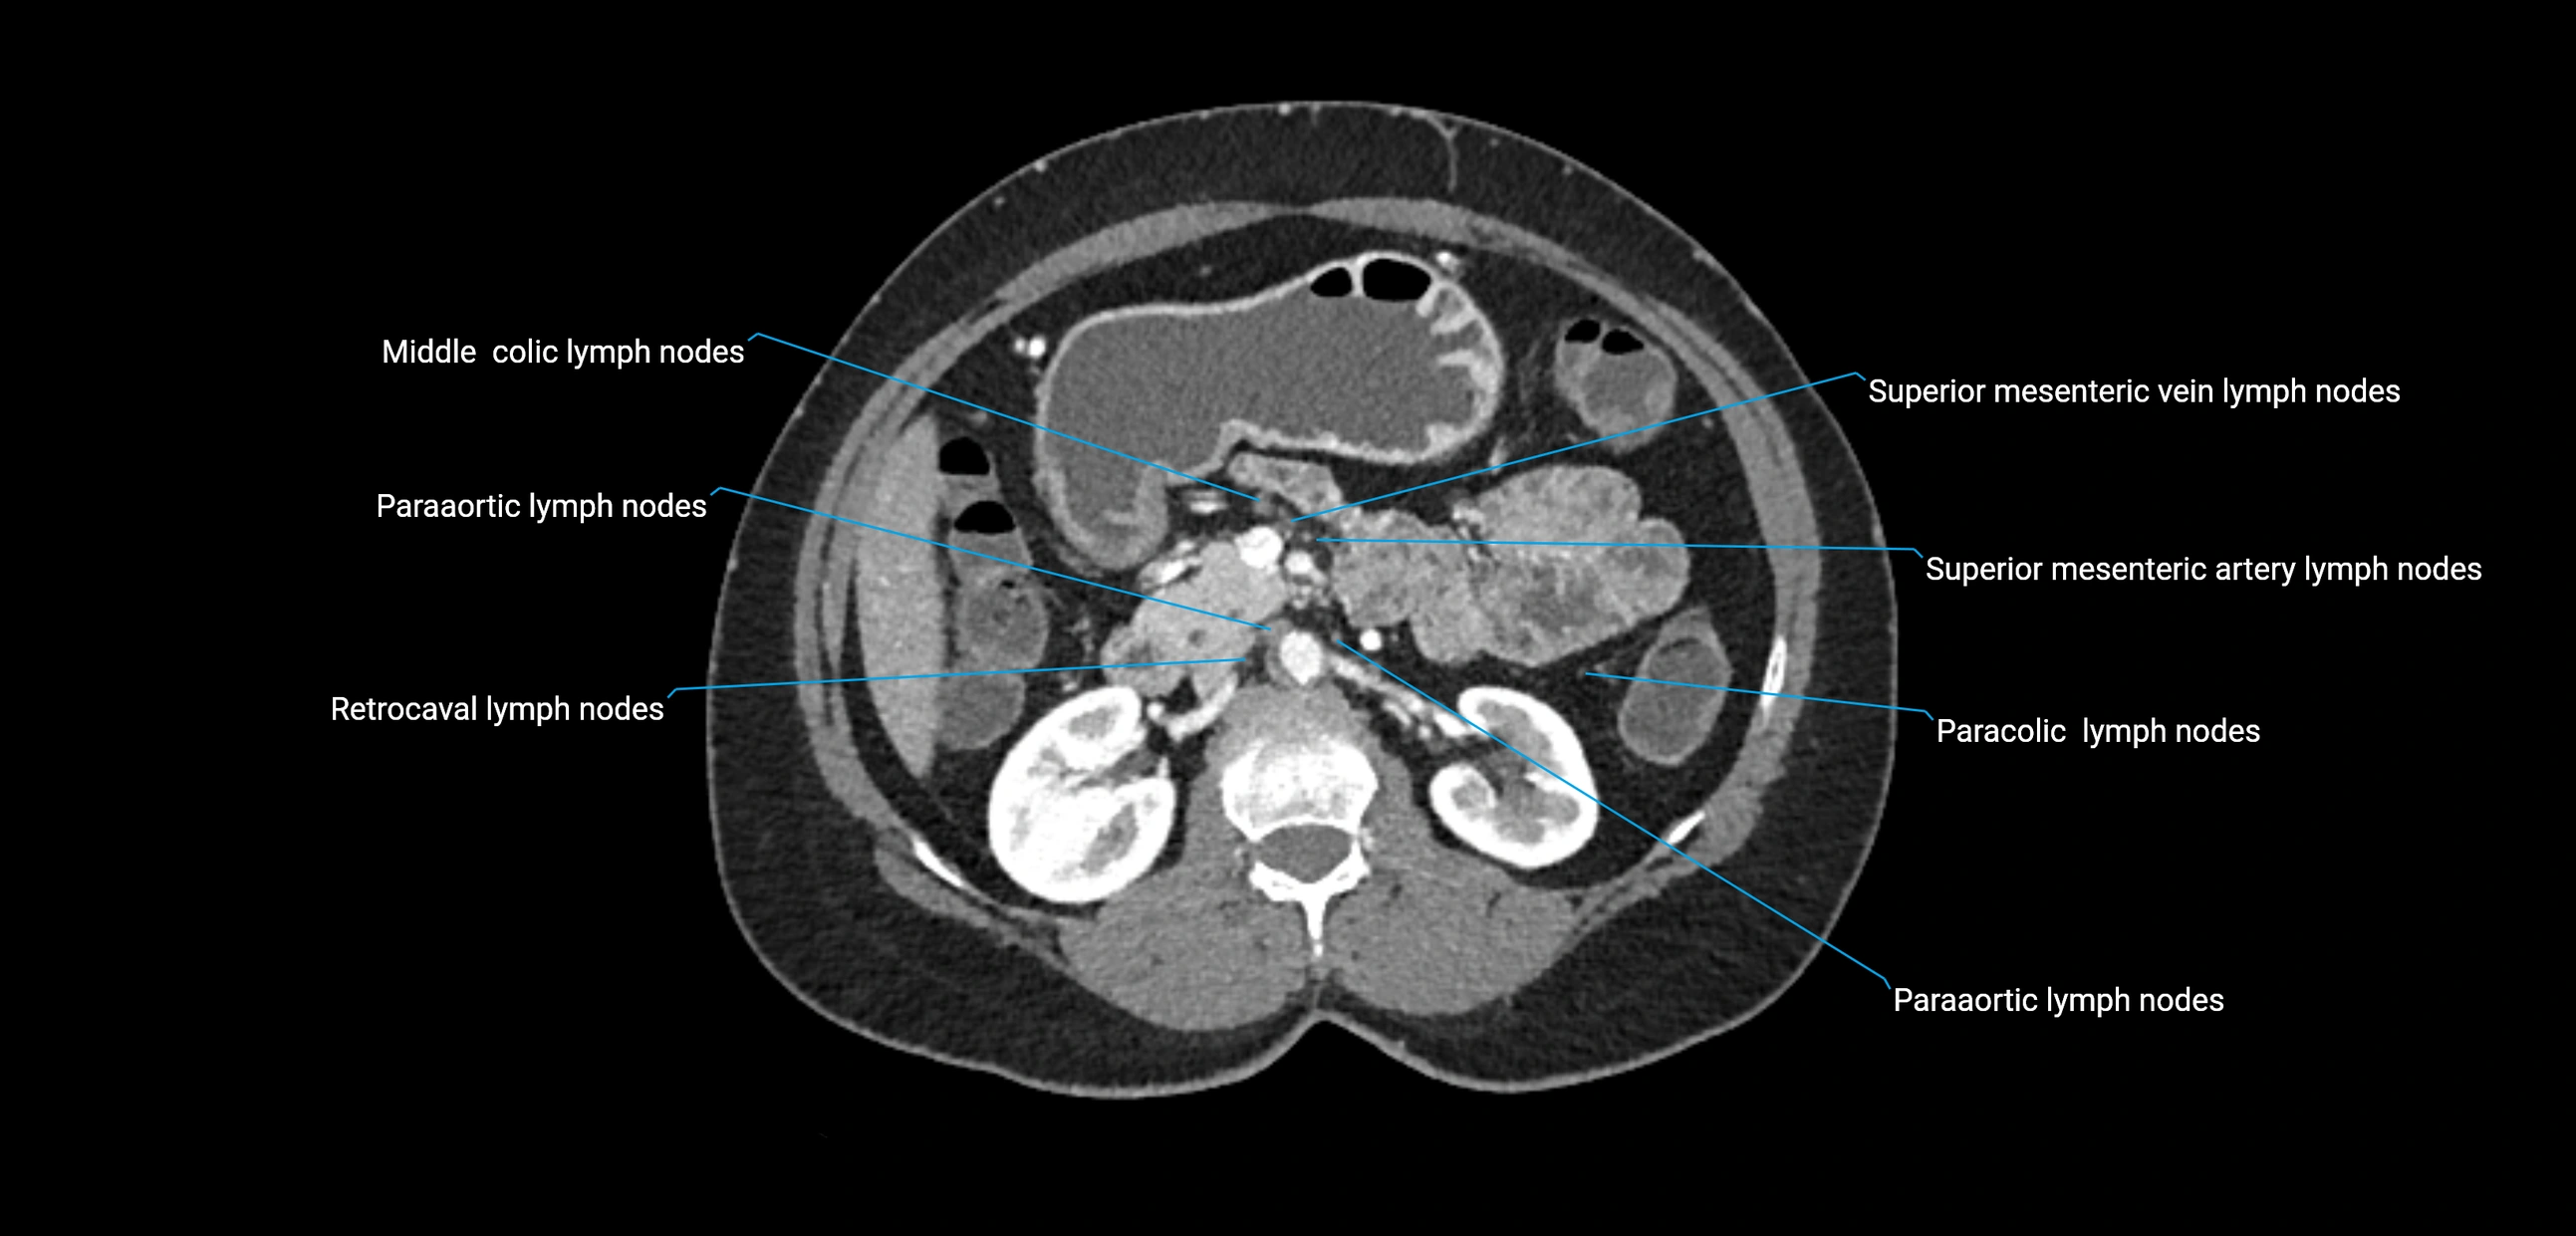

CT image

image